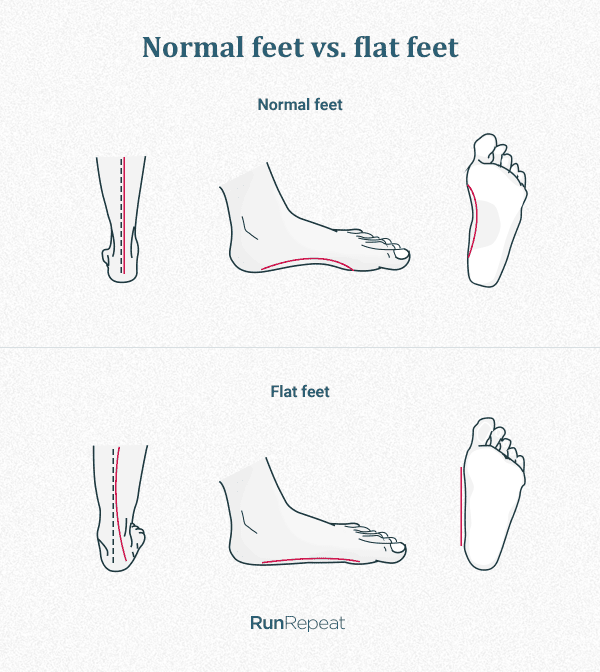

The term “flat foot” is a generic and mis-leading description given for …

Flat Feet and High Arched Feet | Things to Know – Custom Rehab

Flat Foot: Symptoms, Causes And Treatment Of Pes Planus

Flat Foot

Flat Foot | Foot and Ankle Wellness Centre